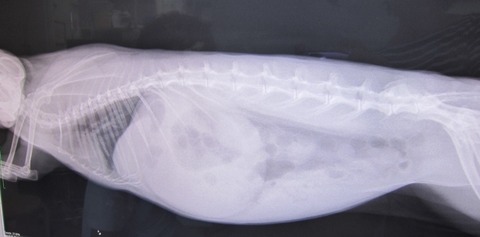

9日の譲渡会、

とてもよく食べ、なでなでアピール頑張ってたかぐらちゃん

排泄物もお見事でした

でも、実は手前の2月6日、ちょっとあったとです夜10時回ってからか、ケージの中で静かに過ごしてたはずなのに、

ふと、気になって近づくと息の上りが秒速になっとる…

もちろん、何を差し出しても食べません。

なでなでしてから祈りつつお風呂入りに行って、戻ってきたら復活?

(赤丸は異変発見すぐに撤収した排泄物)

1つだけやけど出た

その後、牧草もぐもぐから始まっての…

出だした出だした